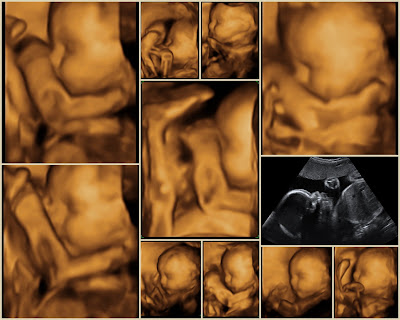

Ultrasound Pics

Baby's Heartbeat is 145 bpm and he's about 2.4 lbs